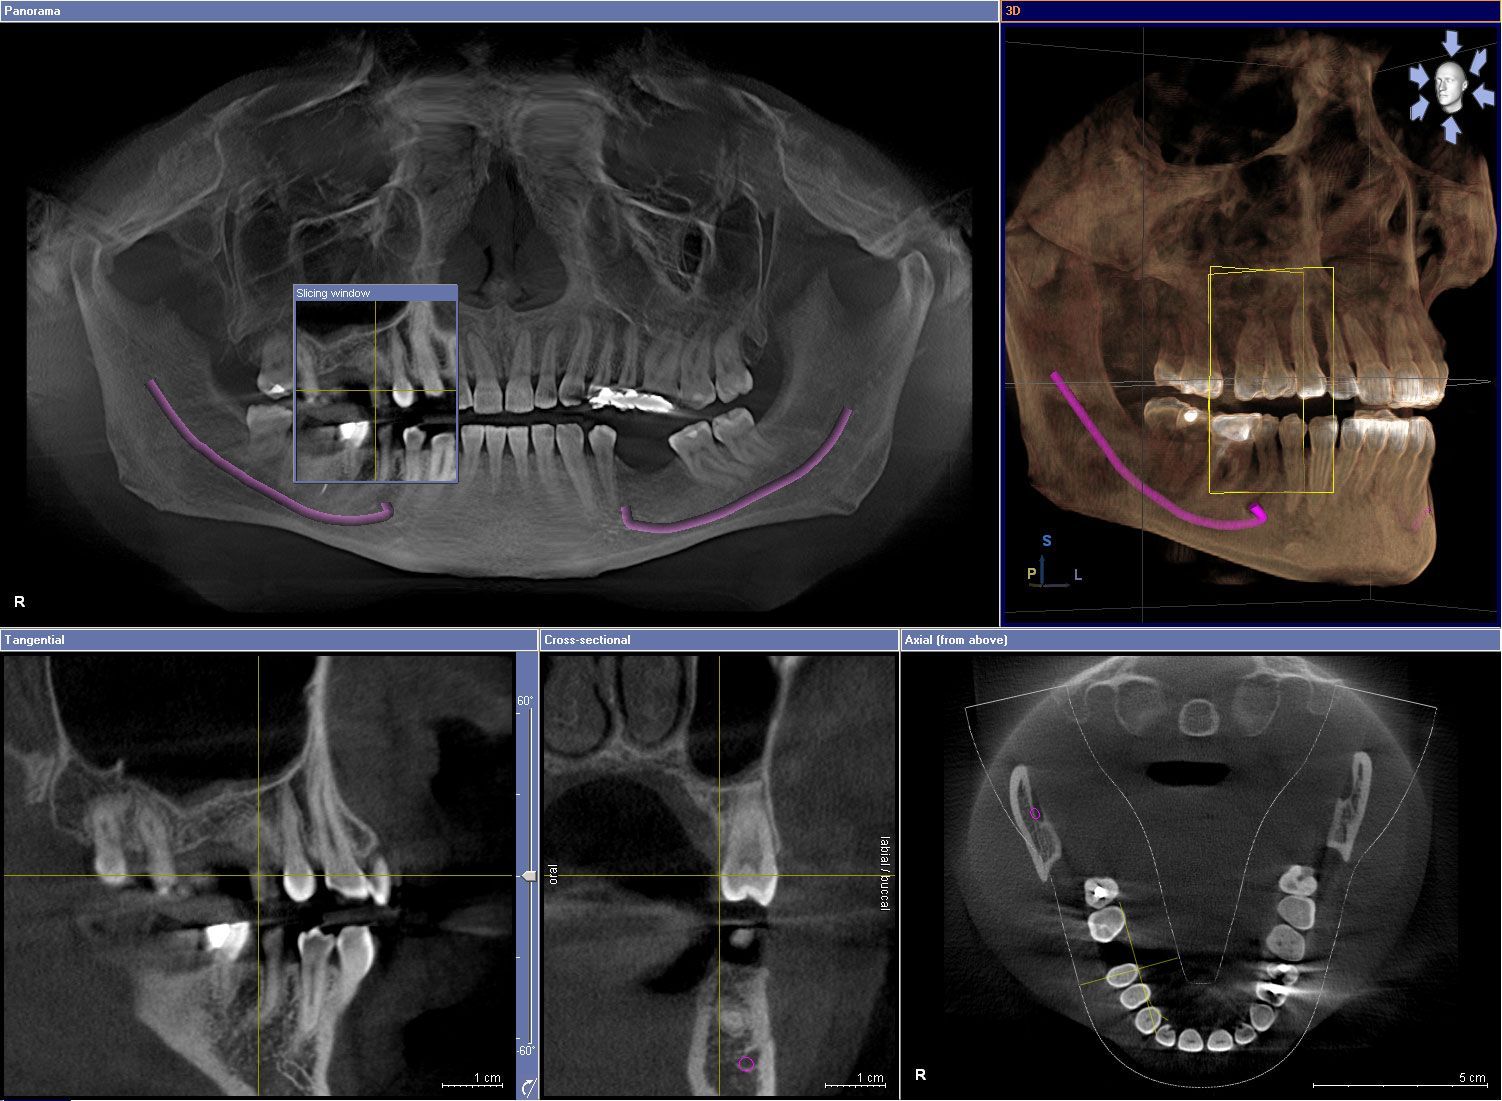

GALILEOS COMFORTPLUS CONE BEAM CT IMAGINg

Images taken with Cone Beam CT are rapidly becoming standard of care. With a single 14 seconds scan, the Galileos can provide our dentists high resolution 3-dimentioal images for more precise diagnosis and treatment planning. Benefits of Cone Beam Imaging include but not limited to the following: